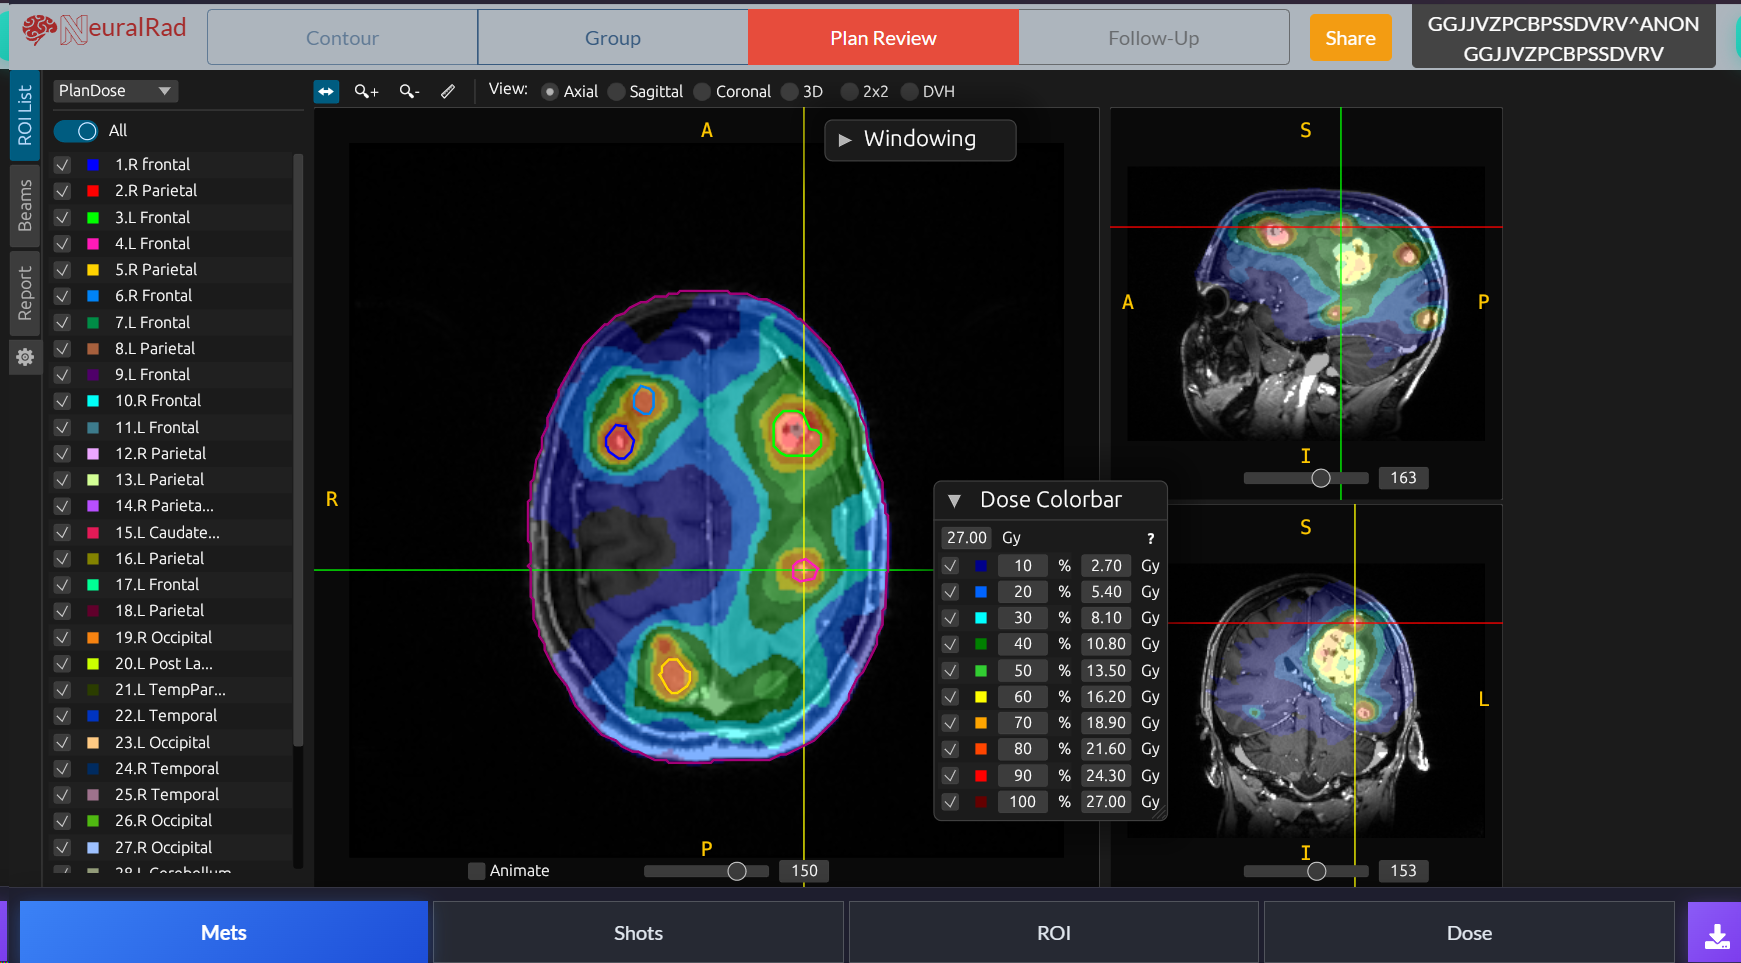

Brain

AI-Powered Stereotactic Radiosurgery Platform

Revolutionizing brain metastasis treatment with automated lesion detection, segmentation, and multi-course tracking. Built for radiation oncologists who demand precision.